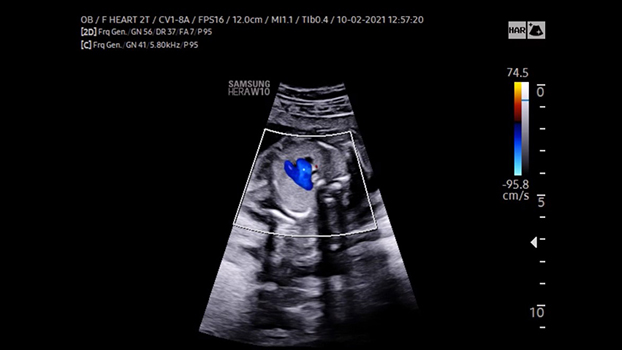

Quest’esame viene riservato solo alle pazienti che hanno una precisa indicazione medica (cardiopatie pregresse, translucenza patologica, diabete scompensato, sospetti di malformazioni evidenziate durante l’ecografia del secondo trimestre ecc.) Viene esaminata con estrema attenzione l’ anatomia del cuore e dei grossi vasi, la continenza delle valvole, l’integrità dei setti ed i ritorni venosi, la velocità di picco della aorta, dell’arteria polmonare e del dotto arterioso. Si valuta inoltre il flusso del sangue che proviene dalla placenta attraverso il dotto venoso.